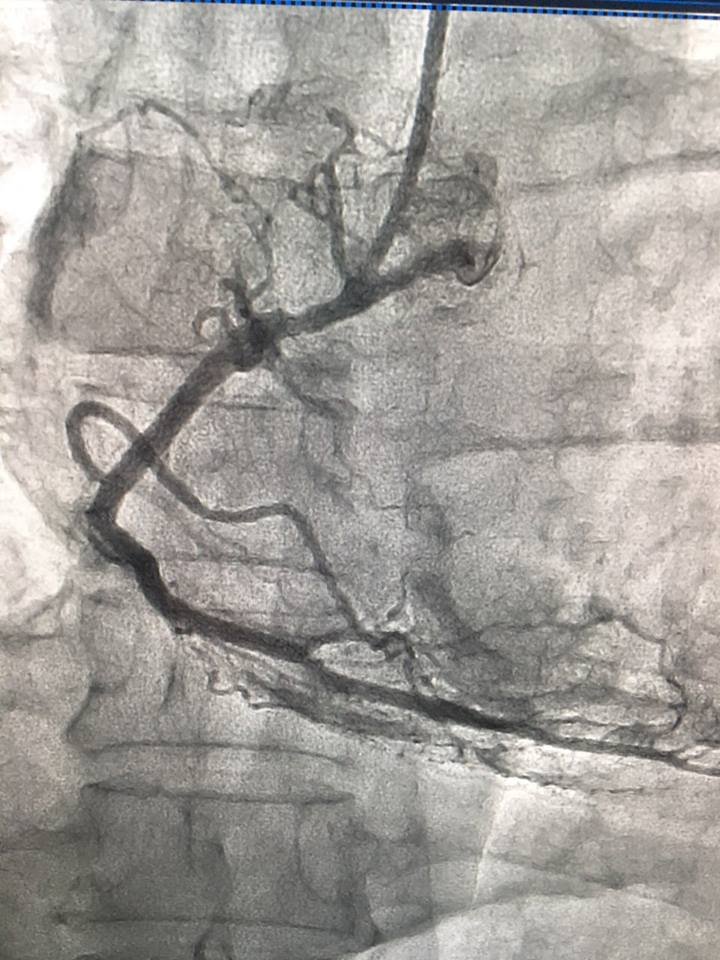

"Сьогодні нашими лікарями за допомогою сучасного ангіографа урнентно проведено стентування коронарних артерій хворому П. з приводу інфаркту міокарда.

Врятоване ще одне життя!!!",- йдеться в дописі.